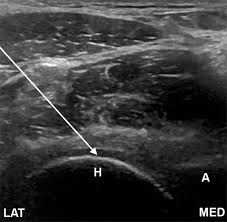

신장 및 요로계 질환

- 신장결석: 콩팥 내 결석 확인 가능

- 수신증: 요관 폐쇄 등으로 신장이 부어 있는 상태 확인

- 신장 종양, 낭종: 악성·양성 종양 여부 1차 판별